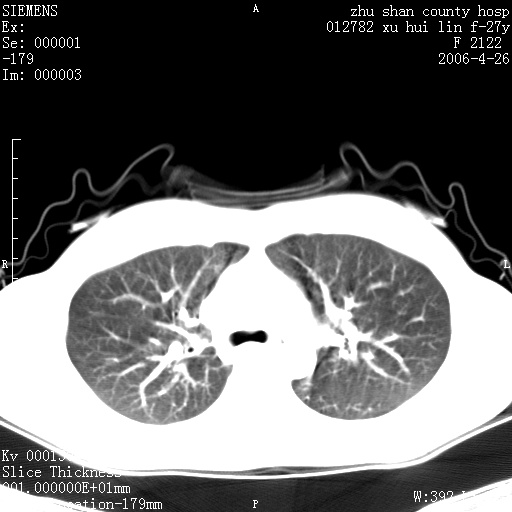

女性 病人 27岁!本院职工家属,五月前因感冒透视发现病变,ct示:左肺下叶背段感染性病变。经过半月规范抗生素治疗后复查病变无明显变化,后行四月规范抗痨治疗,复查无明显变化,后复查无效!请大家帮忙看看!

右肺下叶背段见片状高密度区,边界不清,密度不均,无钙化及空洞影,背段支气管通畅。所见层面肺门及纵隔内未见明显肿大淋巴结影。

诊断:首先还是考虑为慢性炎症。

结核虽然好发于下叶背段,但周围无明显卫星灶,化验结果怎样?